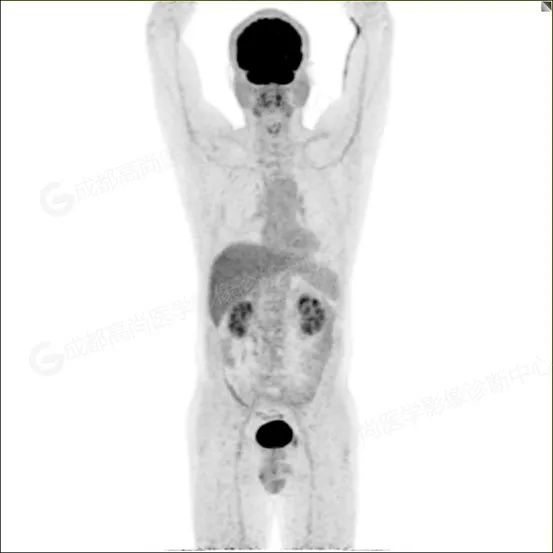

【PET/CT 全身 MIP 图】

PET/CT 检查示:

右肺上叶前段及右肺中叶外侧段分叶状软组织结节,该病变骑跨水平裂胸膜,大小约 1.5 cm×1.3 cm×1.6 cm(上下径),边界清晰,其内密度欠均匀,CT 值约 18 Hu,FDG 摄取未见明显增高。

PET/CT 诊断:1. 右肺上叶前段及右肺中叶外侧段见一分叶状软组织结节影(约 1.5 cm×1.3 cm×1.6 cm),该病变骑跨水平裂胸膜,FDG 摄取未见明显增高,考虑为良性肿瘤,请结合病理协诊。